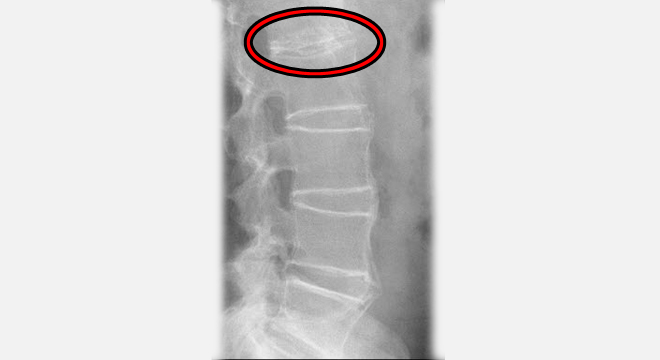

Morbus Bechterew: Röntenbild der Lendenwirbelsäule

• Röntgenbild der Lendenwirbelsäule